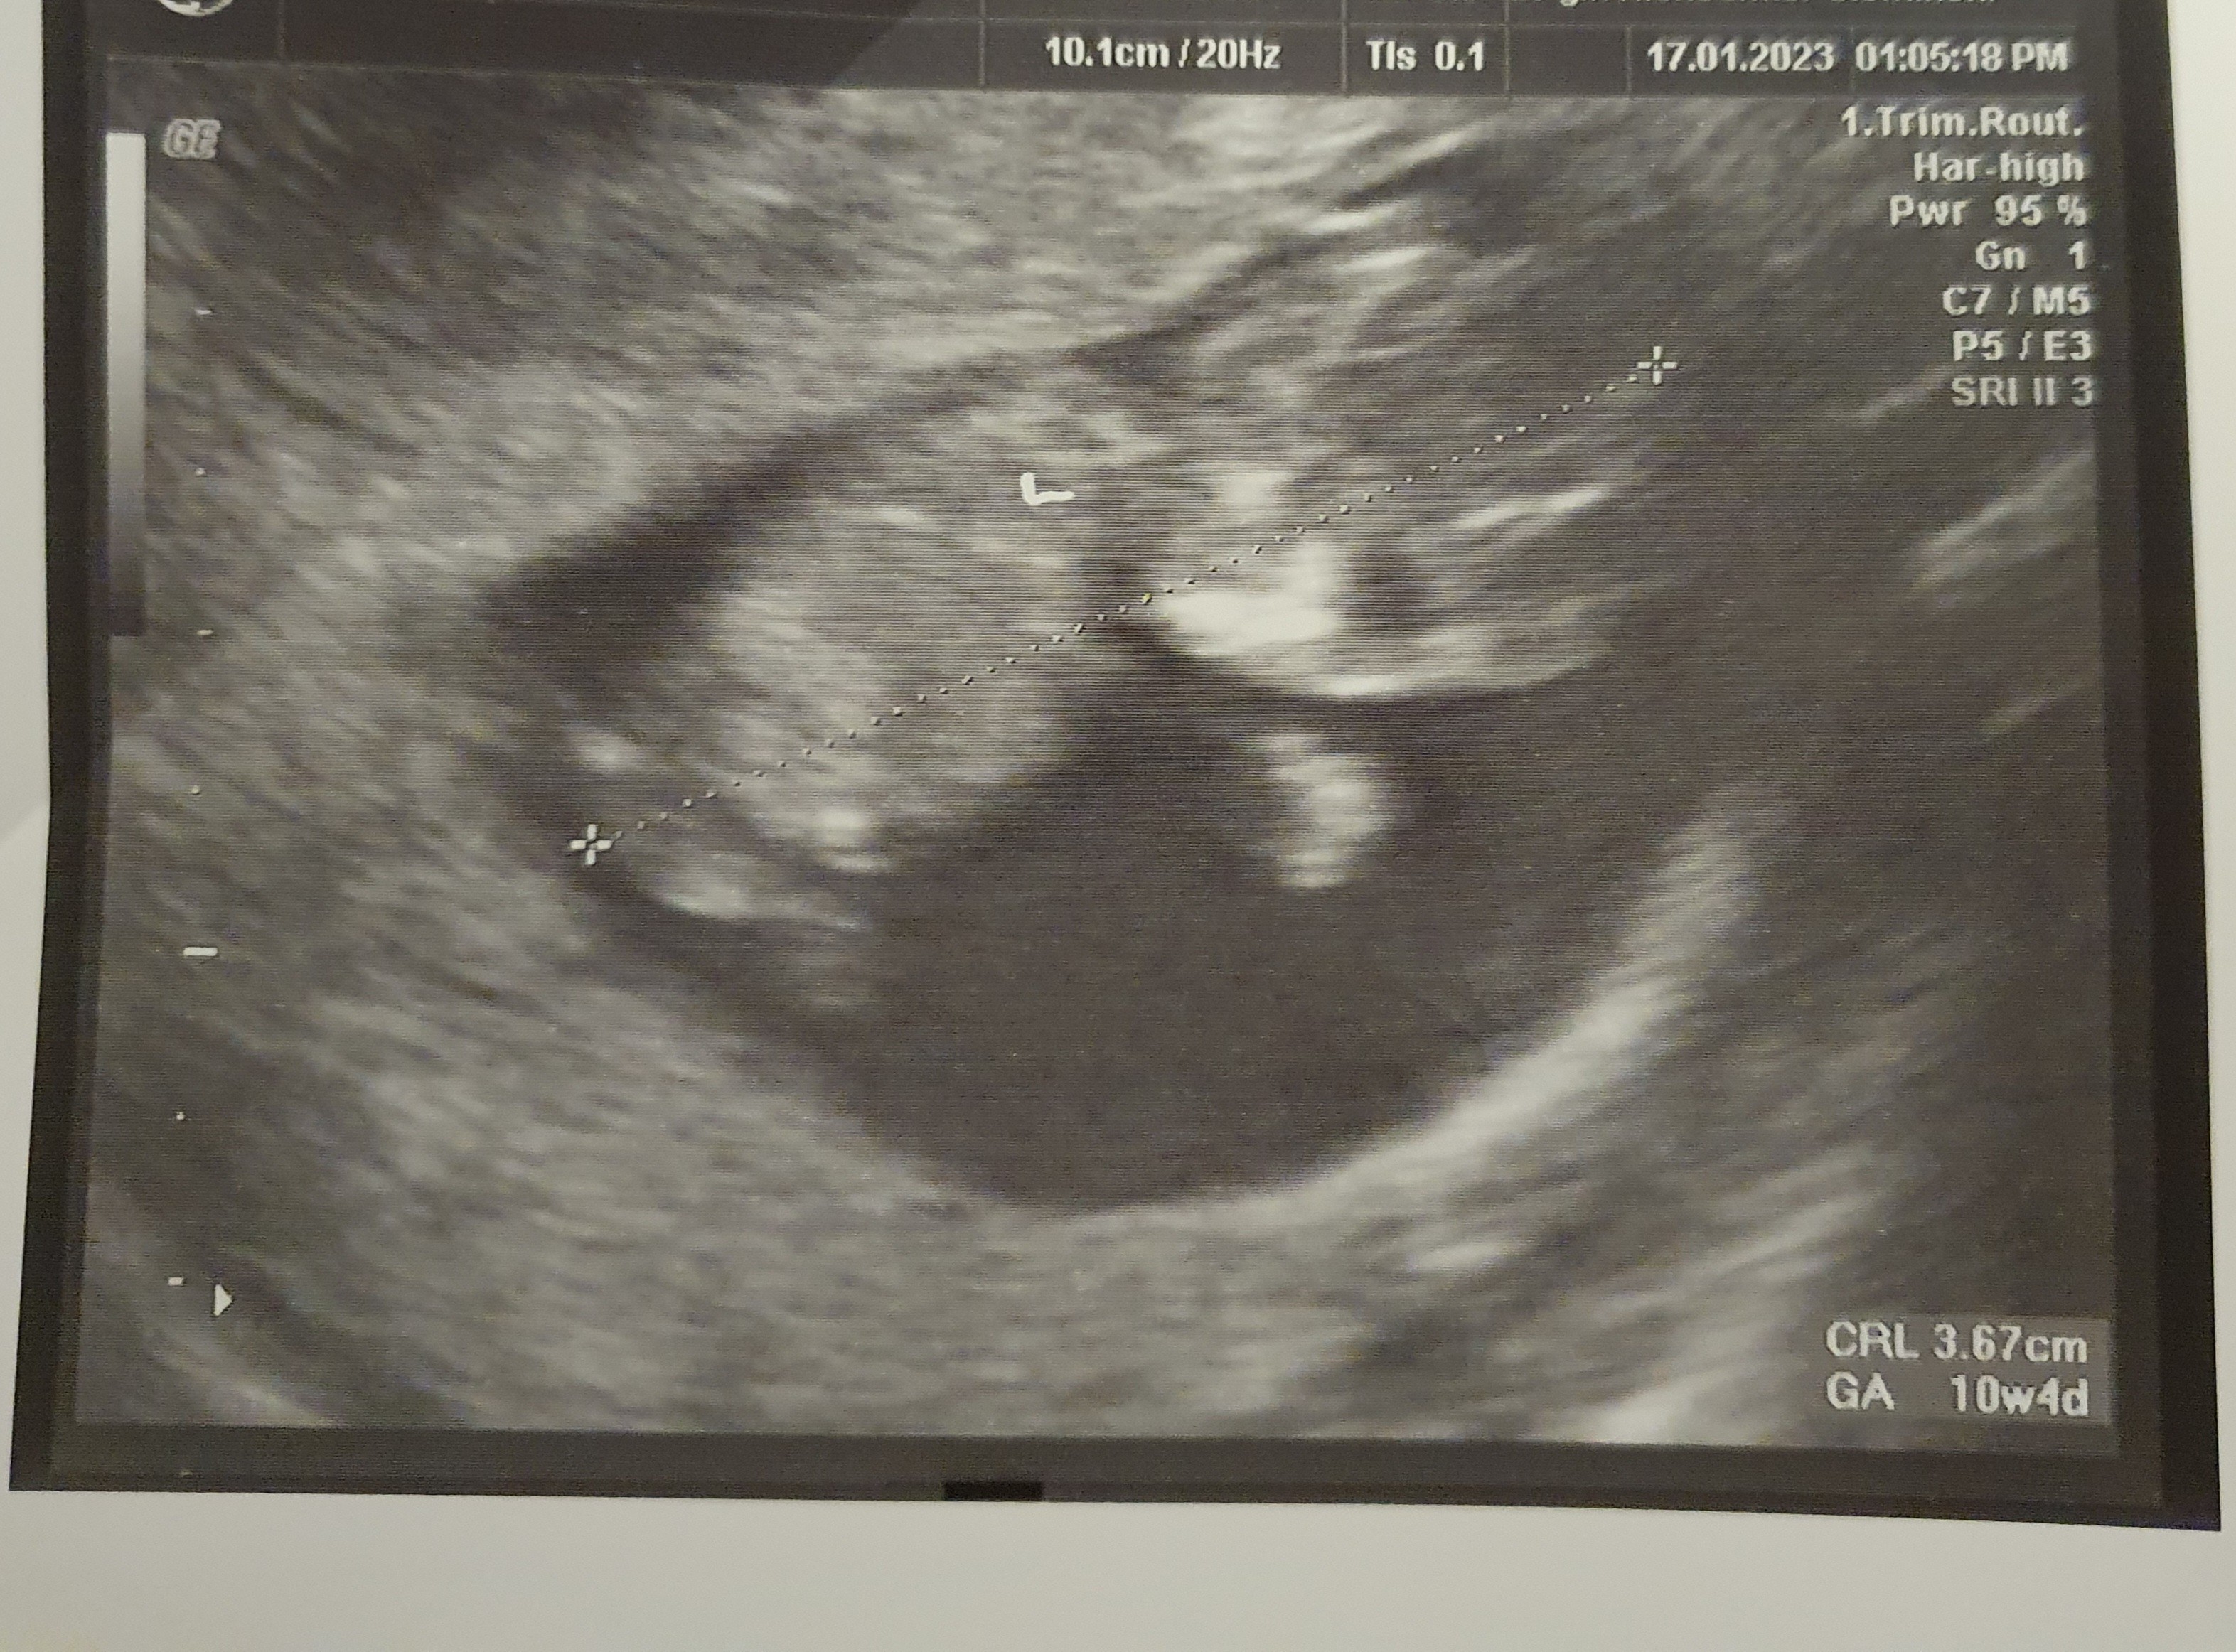

Cześć, dzisiaj bylam u lekarza potwierdzić ciążę i to była moja pierwsza wizyta tez u nowego ginekologa. To moja druga ciąża. Po badaniu usg doktor powiedział ze wszystko jest dobrze, 10t4d. Wypisał skierowanie na badania i na końcu dal skierowanie na badania prenatalne. Troche mnie zdziwiło i pytam czy coś nie tak, powiedział ze nie, badania prenatalne warto robic w ciąży. Ja wiem ale skoro było ok na usg, ja mam 27 lat to skierowanie ? Niepokoi mnie to trochę a na badanie dopiero za 2 tyg. Podobno ten lekarz nie robi problemu żeby wypisać skierowanie w koncu za darmo będzie ale tak sam z siebie dal. Martwi mnie to trochę.😔 poniżej zdjęcie usg i co na skierowaniu dopisał przy zaznaczonym podpunkcie.

• 20230117_200818.jpg

20230117_200818.jpg

1,5 MB · Wyświetleń: 598